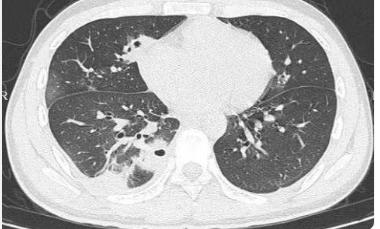

刷到20岁男生肺被查出10多个空洞的新闻,我直接惊掉下巴!本该是跑跳都带风的年纪